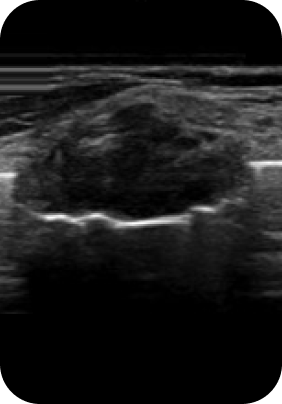

맘모톰, 비후성/알레르기 비염, 비중격 만곡증, 비밸브 협착증 등

질환에 따라 3DCT, 내시경 검사, 고해상도 초음파를 통해 정밀진단 후

정확한 증상에 따라 보험 실비 청구가 가능합니다.

대학병원급 검사 장비

디에이성형외과에서는 대학병원급 검사 장비 시스템

각 분과의 전문의와 성형외과 전문의가 협진하여